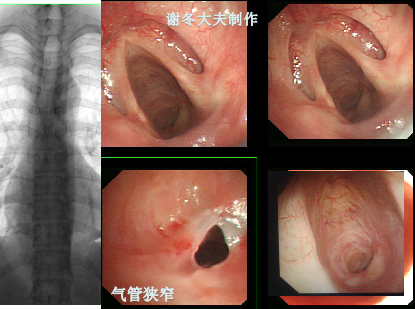

气管狭窄气管插管气管切开后狭窄是什么如何治疗